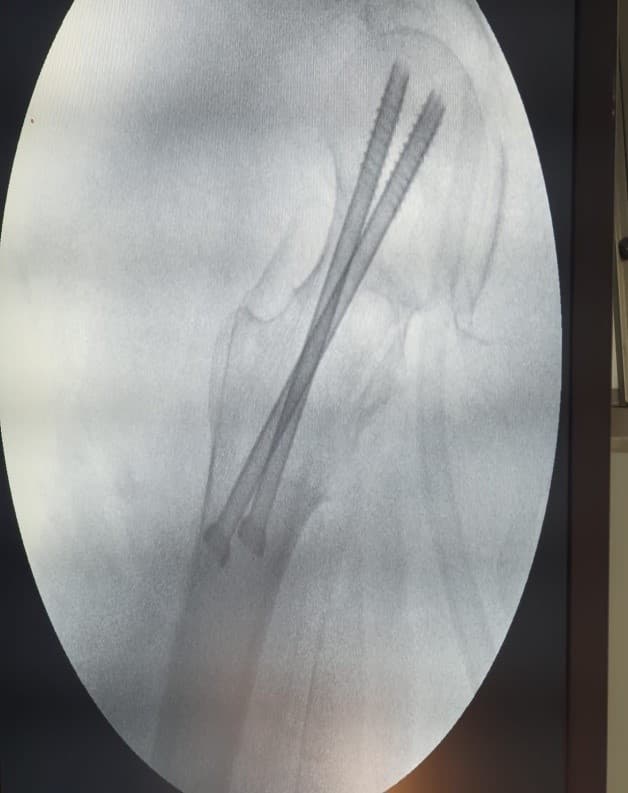

Internal Fixation-хагалгаа, дотор бэхэлгээ / тусгай хадаас

Хугарал засах мэс засал image4

DHS - Дунд чөмөгний гадна бэхэлгээ

Хугарал засах мэс засал image5

УНТЭ-т хийгдсэн мэс заслын зураг

Hip screw-Түнхний шураг

Хугарал засах мэс засал image6

Хугарал засах мэс засал image7